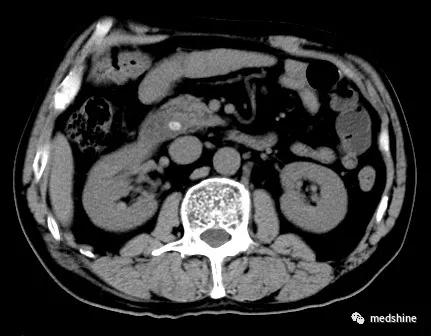

4、胆总管残余结石或新发结石

部分胆囊结石患者合并胆总结石,如果术前或术中没有发现胆管结石单纯实施了胆囊切除手术,就会导致胆总管残余结石,术后可能会出现相应的问题。还有少数患者在胆囊切除多年以后新发胆总管结石。

胆总管结石

对于胆总管结石,如果大于3.5mm,不论有无症状,一旦发现都应进行治疗。目前主要有内镜下oddi括约肌切开取石和腹腔镜联合胆道镜手术取石两种方法,应根据具体情况合理选择 。